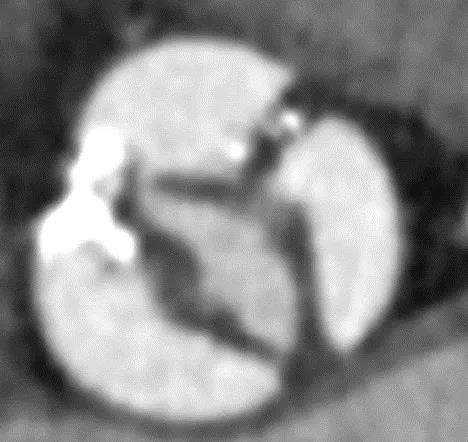

经术前详尽影像学重建、评估及病例讨论,最终决定在脑氧监测下对患者实施经左侧颈总动脉TAVI手术。术中左侧颈总动脉多次预扩后顺利置入血管鞘至升主动脉,跨瓣成功后先以23#球囊预扩,再“0位”植入25# Renatus介入主动脉瓣。手术耗时约2小时,介入主动脉瓣植入位置理想,功能表现良好,主动脉瓣峰值流速及平均跨瓣压差分别降至1.75m/s和5mmHg,造影及TEE观察仅有轻微瓣周漏,无中央型反流。术后左颈总动脉造影无明显狭窄,手术全程脑氧饱和度正常,无传导阻滞、无冠脉异常。

瓣膜“0位”释放 术后主动脉根部造影